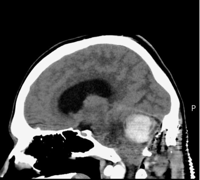

In July 2025, Luke was diagnosed with a haemangioblastoma - a very rare brain tumour.

By the time of diagnosis, the tumour had grown so large - bigger than a golf ball - that Luke was told he only had days to live without emergency surgery.

Luke Taylor's brain scan. (Nia Jones via SWNS)